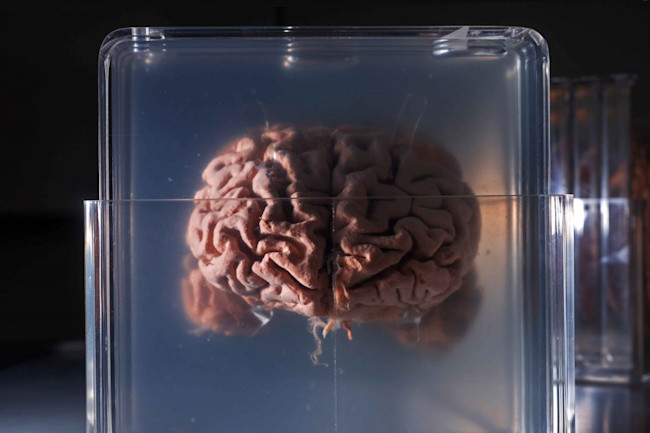

As we saw earlier, the human brain is about three times as big as expected in a primate of our size. Listen free to The Pillows – NOOK IN THE BRAIN (Envy, 王様になれ and more). I hope you all stay healthy and safe.

The brain the story of you Sep 07, Posted By David Baldacci Library TEXT ID 5263b318 Online PDF Ebook Epub Library the year setting out the state of find books like the brain the story of you from the worlds largest community of readers goodreads members who liked the brain the story of. Moreover, the brain is at its most impressionable while it is growing. Nook in the brain really amps it up from their previous installments.